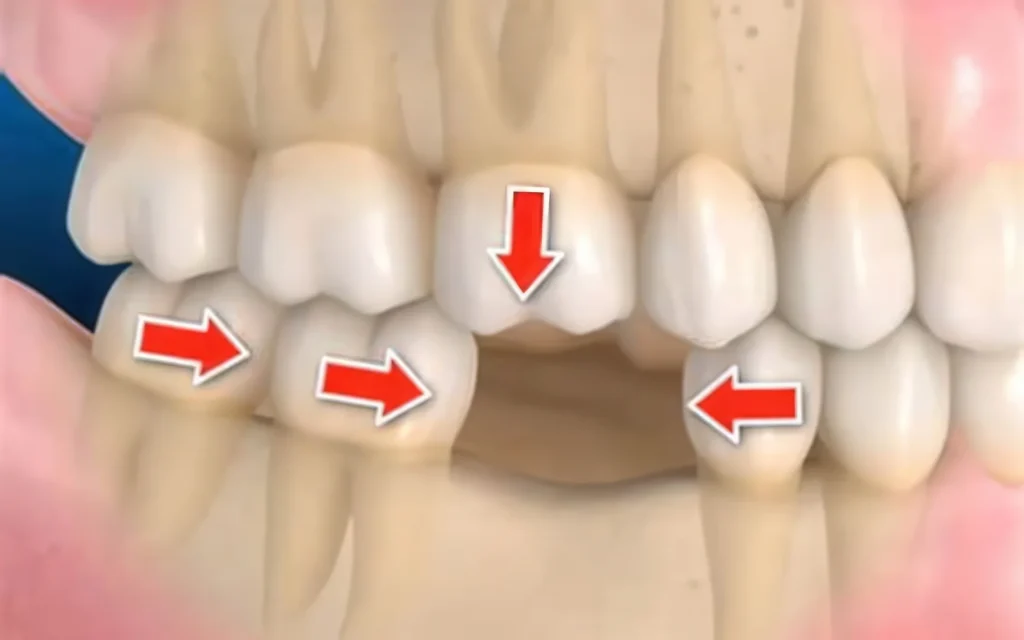

Потеря зубов и «провал» прикуса

Один отсутствующий моляр — и нагрузка перекраивается. Соседние зубы мигрируют, прикус уплощается, сустав ищет новую траекторию, а мышцы живут в режиме компенсации.